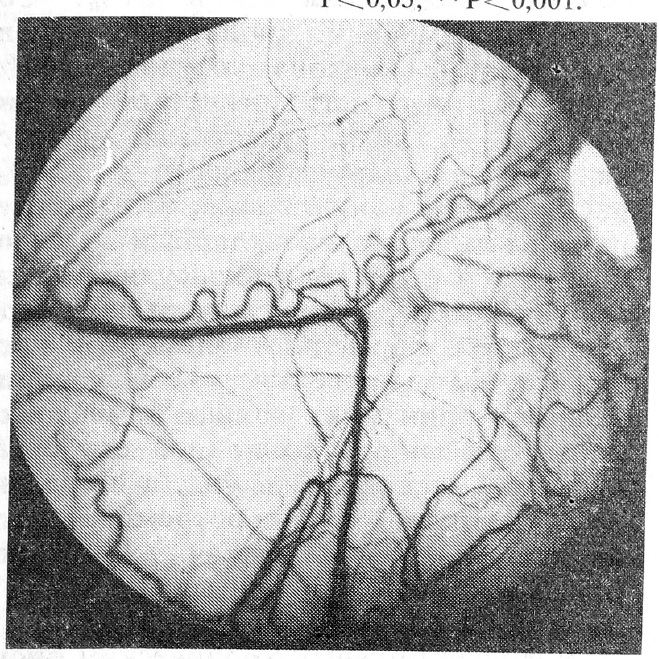

При поступлении в стационар у всех больных были нарушения состояния микроциркуляции, характеризовавшиеся периваскулярными, сосудистыми и внутрисосудистыми изменениями, нараставшими параллельно тяжести заболевания (рис. 1). Периваскулярные изменения у больных неспецифическим заболеванием легких были вызваны разлитым (у всех больных с тяжелой пневмонией) или локальным периваскулярным отеком в 45% случаев, мелкоточечными кровоизлияниями — в 20% и очагами гемосидероза — в 37%. Сосудистые изменения проявлялись неравномерностью калибра сосудов у 65% больных, их патологической извитостью — у 100%, «участками запустевания» капиллярного русла — у 50%, расширением капилляров и венул, нарушением артериоловенулярных соотношений — у 90%. Внутрисосудистые изменения были обусловлены выраженной агрегацией форменных элементов крови, которая приводила к нарушению микрогемодинамики в виде замедления кровотока вплоть до полной его остановки на несколько секунд, а в отдельных случаях — к микротромбообразованию. Феномен «сладжа» 3.3.КIII наблюдался у 35% больных, 2.2.КII — у 60% и 1.1.КI — у 5%.

Рис. 1. Микрофотография бульбарной конъюнктивы больного К., 40 лет, до лечения, х25 раз. Диагноз: хронический обструктивный бронхит в стадии обострения.